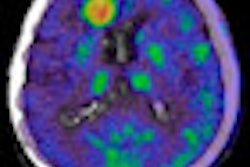

Results from the company's phase II clinical trial at six sites suggest that technetium-99m (Tc-99m) ethylene dicysteine deoxyglucose (ECDG) with SPECT can localize primary and metastatic lesions and is not inferior to FDG-PET in image quality or performance.

ECDG has shown potential in coronary artery disease imaging as well. Click here to read more.